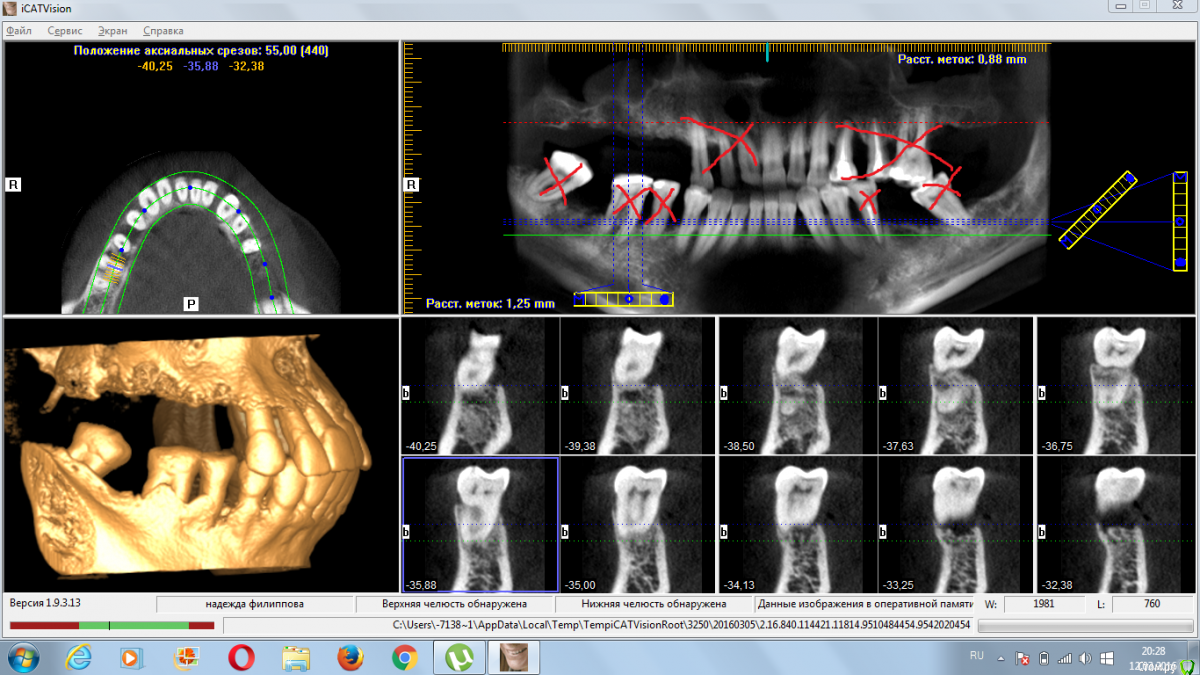

4ebstom Опубликовано 12 марта, 2016 Поделиться Опубликовано 12 марта, 2016 Коллеги,прошу помощи в плане лечения.36 лет,Ж.Не устраивает ЧСПП.Отмечает резкое расшатывание зубов.Соматику отрицает. Предварительно прикинул план лечения:1.Удаление2.Имплантация во всех сегментах.(синусы+нкр)3.Проф.чистка.Собственно вопросы:1.Как быть с утолщением слизистой пазух?Консультация ЛОР?2.Кюретаж открытый или?3.Как быть с протрузией?Ваши замечания и коррективы?Спасибо всем откликнувшимся. Ссылка на комментарий

Доктор Дмитрий Опубликовано 12 марта, 2016 Поделиться Опубликовано 12 марта, 2016 По поводу пазух- надо кт повыше сделать, скорее всего соустья свободные и оперировать можно. Вы сузили показания для удаления,по крайней мере на вч надо все удалять, даже если оставить 2,1 2,2 2,3 под временную опору- это ничего не даст. Импланты можно установить по шаблону. Можно обойтись без синусов, если по другому распланировать хирургию, например- все на 4. 1 Ссылка на комментарий